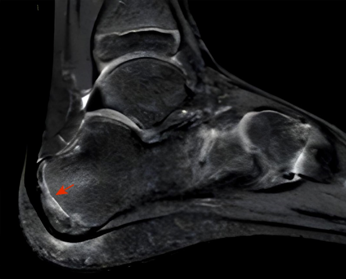

图5:核磁共振示骨骺密度最高(箭头)